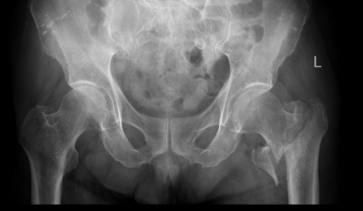

患者张爷爷已逾九旬,基础疾病错综复杂:前列腺癌病史3年、高血压20年、糖尿病30年,10天前因脑梗死导致左侧肢体活动不便。然而近日,厄运再次降临,他在家如厕时不慎跌倒,造成“左侧股骨转子间粉碎型骨折”,被紧急送至二一五医院。

入院时,老人情况十分危急:除骨折外,还存在Ⅰ型呼吸衰竭、慢性支气管炎急性加重、低钠血症及贫血。入院后其呼吸功能进一步恶化,随即被转入ICU,进行气管插管、呼吸机辅助呼吸。经过ICU团队5天昼夜不停的全力救治,张爷爷的呼吸功能终于显著改善,成功拔管,脱离了生命危险。

闯过呼吸衰竭的第一关后,另一个严峻问题摆在面前:左髋部粉碎性骨折带来的剧痛与长期卧床风险,对于这位刚从ICU转出的老人而言,极易引发肺部感染、血栓、褥疮等严重并发症,可能导致前功尽弃。

ICU与呼吸内科团队确保患者拔管后呼吸功能稳定;心血管内科、内分泌科精准调控血压、血糖至精准范围;神经内科评估脑梗后状态。手术麻醉科量身定制创伤最小、最稳定的个性化麻醉与监测方案,严阵以待可能出现的循环呼吸波动。在此基础上,骨科团队最终决定采用微创的“闭合复位髓内钉内固定术”,力求以最短时间、最小创伤完成固定。

在万全准备下,手术如期展开。术中,多学科团队配合默契,操作精准流畅。仅用时40分钟便成功完成骨折复位与固定,术中出血极少,患者生命体征平稳。这场高风险手术取得了关键性胜利。